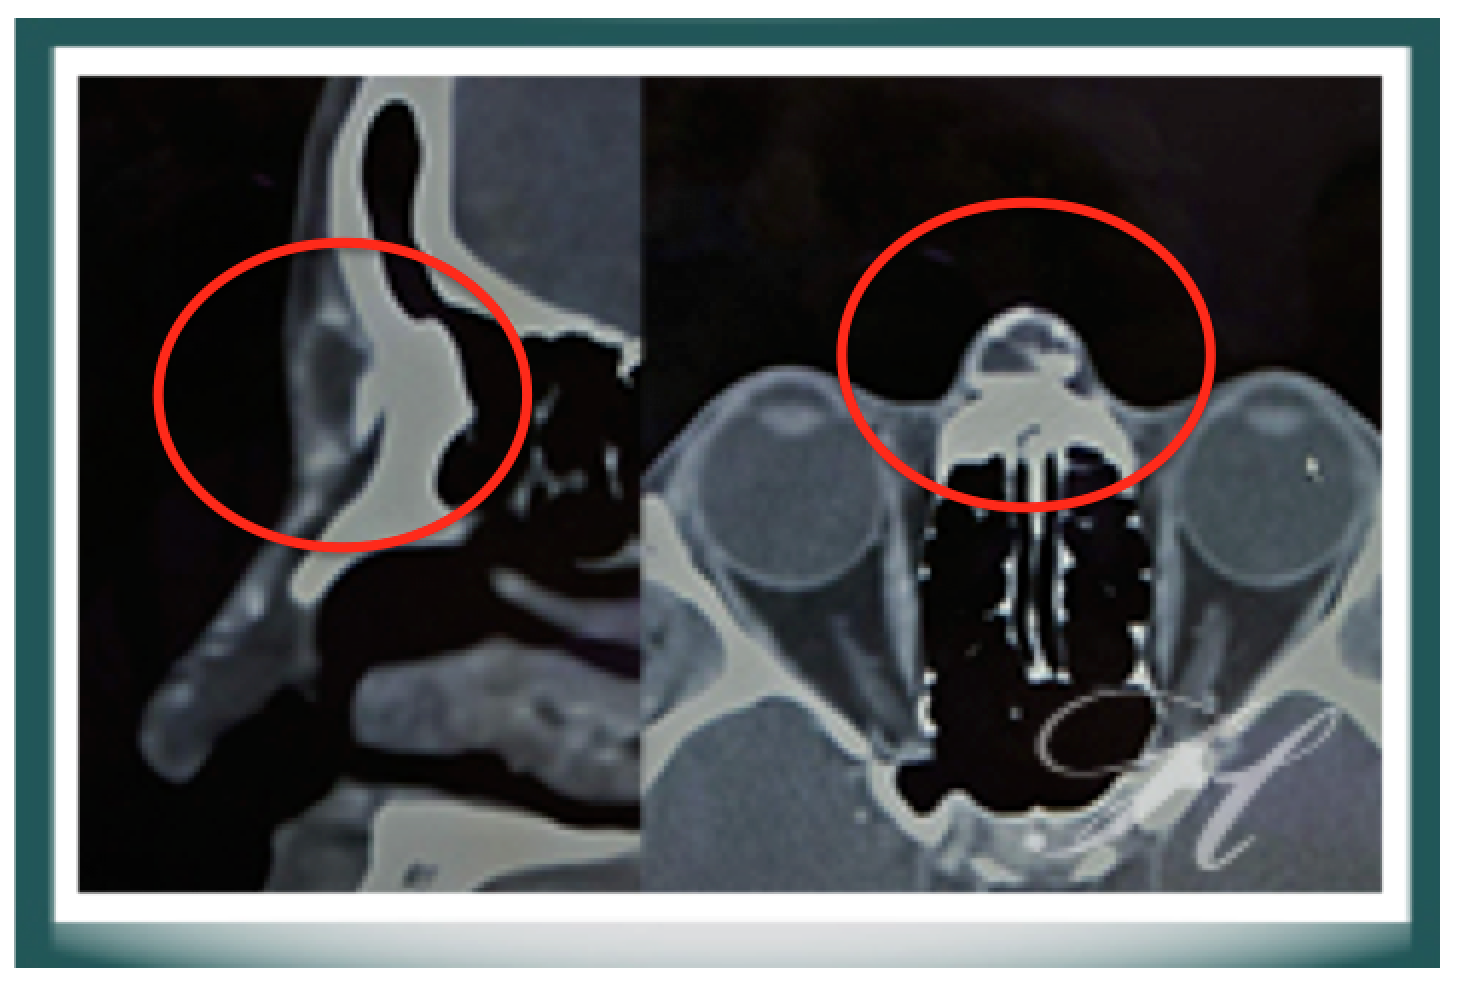

(圖六)利用微晶瓷注射山根後造成局部肉芽組織增生及皮下異物組織反應。利用斷層掃描發現皮下有微晶瓷所產生的鈣化現象(Calcification)和異物反應後的組織液增生(Seroma)。